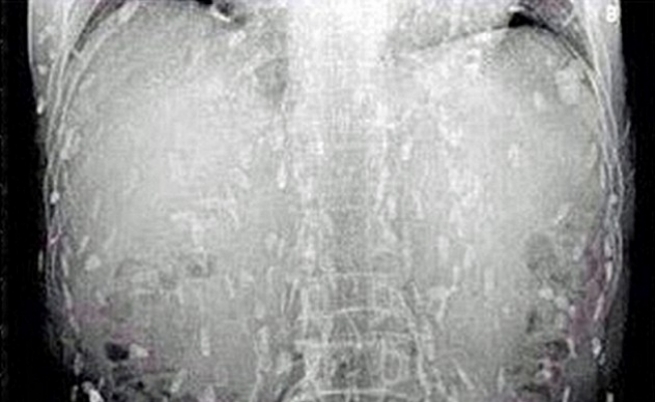

La radiografia di un paziente ha svelato la presenza di larve nel tratto gastrointestinale causate forse da parassiti trasmessi dal maiale poco cotto.